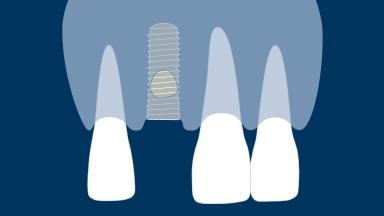

On the basis that implants should always be placed in an ideal three-dimensional prosthodontic position, peri-implant defects in the bone and soft tissues are often encountered when implants are placed. If these defects are minor, they can be treated at the time of implant placement with a high degree of predictability.

This module will deal with the management of peri-implant hard and soft tissue defects resulting from post-extraction tissue changes.